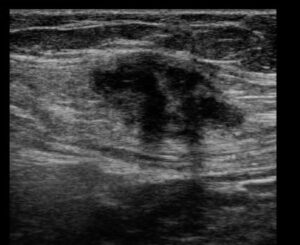

A ultrassonografia de parede abdominal confirma o diagnóstico e auxilia no planejamento da cirurgia, fornecendo informações importantes, como quais camadas da parede abdominal estão acometidas e tamanho da lesão.

O exame de ultrassom é realizado no próprio consultório, após o exame físico, já confirmando ou afastando a possibilidade de endometriose na cesárea.